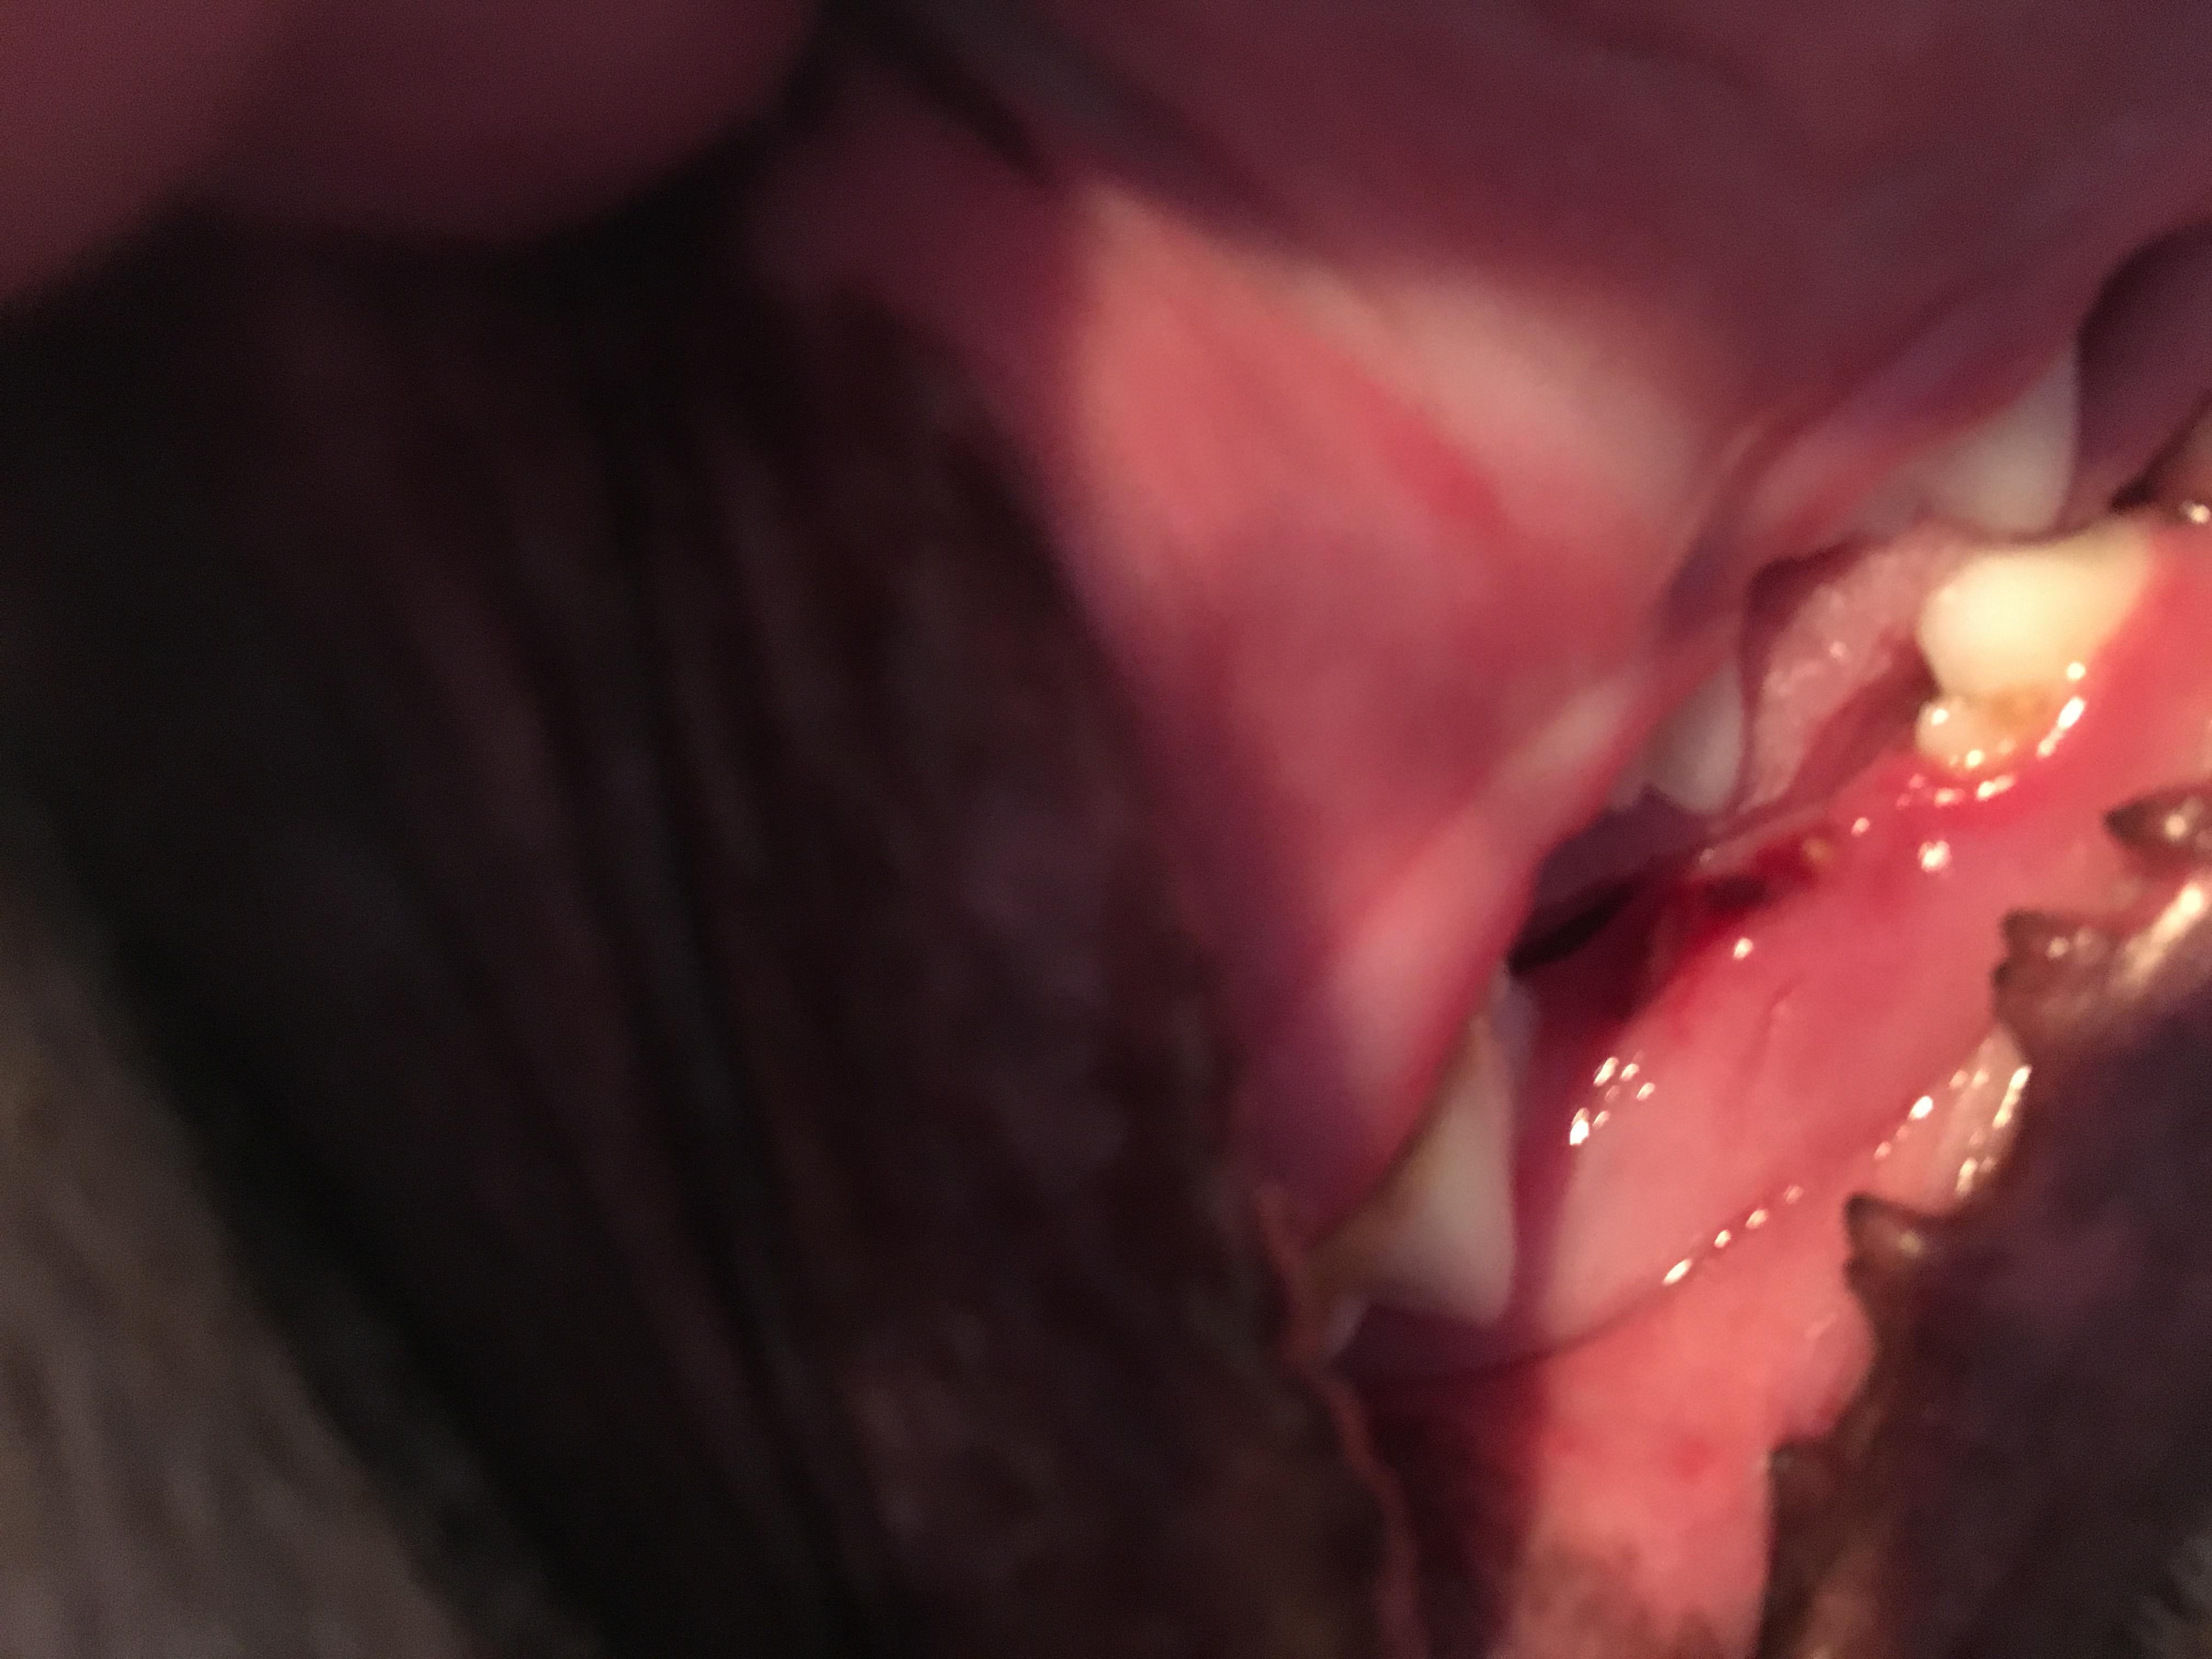

What did my dog do to his tooth ?? He’s 9 month old. I don’t think he lost a baby tooth the gap looks huge. I attached pictures of both sides of his bottom jaw. First photo is missing tooth. Second photo is opposite side(but top jaw in photo is actually bottom teeth ) to compare the gap. Third photo is bloody tooth socket.

There is definitely a tooth missing there and it should not be a baby tooth unless the permenant tooth has a delayed eruption. For a permenant tooth to be dislodged like this, it would take a lot of force and would likely have fractured the root. If you know of a recent event that would have caused this to happen, then it would be best to have a vet examine him. They can take x-rays and check for the broken root. If there hasn't been a a recent epsisode of trauma and Zeek is otherwise normal and healthy, then you can wait and monitor him for a month or two to see if there is a permenant tooth that erupts (assuming this is a delayed eruption). I would definitely alert your vet about this if he is over a year old and there is still no tooth, or he has any swelling or other signs of infection/problems in the meantime. I hope that helps and all is well with Zeek.